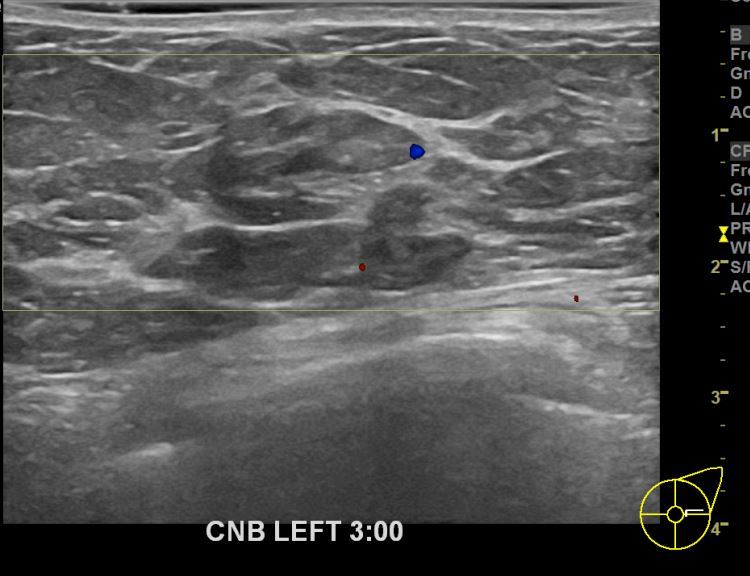

아산유외과개원후 668번째 유방암진단

상기환자 외부검사상 이상소견으로 내원하신 60대여성으로 좌측에 의심스러운혹 조직검사시행해 유방암 진단되었습니다.